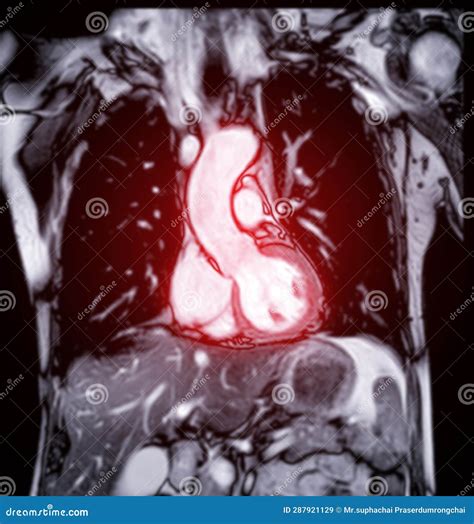

An MRI of heart, or cardiac magnetic resonance imaging (CMR), uses magnetic fields and radio waves to produce detailed images of the heart. Unlike traditional X-rays or CT scans, which use ionizing radiation, MRI relies on magnetic resonance, making it a safer option for repeated examinations. This technology is particularly valuable for diagnosing a wide range of cardiac conditions, from congenital heart defects to heart disease and heart failure.

The process of obtaining an MRI of heart involves several steps. Patients are typically asked to lie on a table that slides into a large, cylindrical machine. The machine generates a strong magnetic field and uses radio waves to create images of the heart. During the procedure, patients may be asked to hold their breath for short periods to minimize movement and improve image quality. The entire process usually takes between 30 to 60 minutes.

• Contrast-enhanced MRI: By injecting a contrast agent, cardiologists can enhance the visibility of certain structures and detect abnormalities more effectively.